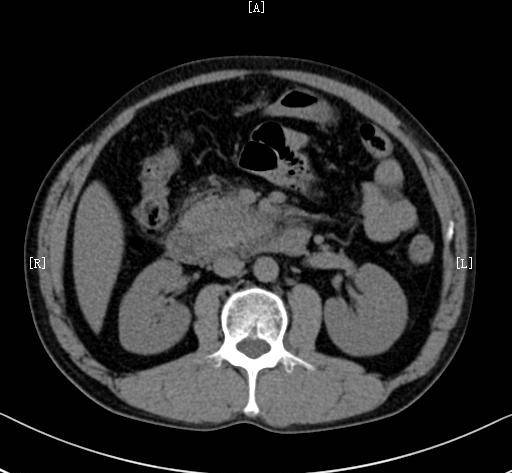

腹部ct可见明显胆总管扩张增粗,其内多发结石,肝内胆管也伴随扩张

术前增强ct检查提示胆管胰管均扩张